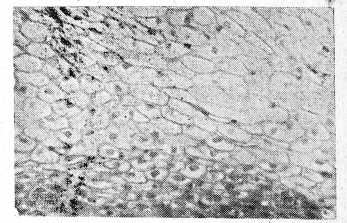

При гистологическом исследовании обнаружено своеобразное строение опухоли, идентичное в 1-м и 2-м наблюдениях. Строма опухоли не содержит желез. Эпителий выстилает в основном не сосочки, а щели стромы и характеризуется зональностью расположения клеток, подобно переходноклеточному эпителию мочевых путей (рис. 1).

Рис. 1. Инвертированная папиллома носа. Общий вид опухоли. Эпителий характеризуется зональностью расположения клеток в три слоя. Гематоксилин-эозин. ˟56.

Базальную зону составляют темные мелкие клетки, промежуточную—светлые и крупные, поверхностную — уплощенные (рис. 2).

Рис. 2. Клеточные элементы эпителия инвертированной папилломы носа. Базальный слой представлен темными мелкими клетками, промежуточный — светлыми и крупными, поверхностный — уплощенными клетками, Гематоксилин-эозин. ˟ 280.